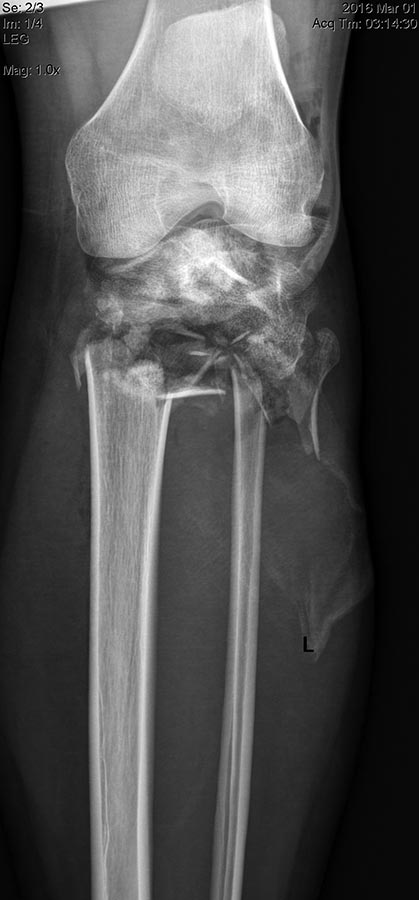

Уважаемые коллеги! Поступила пациентка после получения травмы в

результате столкновения с препятствием.

Открытые (3a-b) оскольчатые внутрисуставные переломы проксимального

отдела обеих костей правой и левой голени. (см. снимки)

пластиной. Что делать с переломами костей левой голени, пока не решили

окончательно. Пока мнение коллег такое: оставить все как есть до

заживления /консолидации и ортопедические проблемы с коленным суставом и

укорочением (3-4 см) решать в отдаленном периоде эндопротезирование (?).